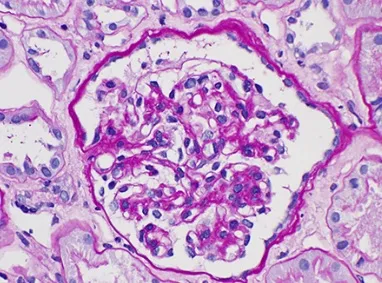

Será que o tratamento de Prurido na Hemodiálise deve se concentrar apenas no controle do Fósforo? Confere dicas simples e práticas de como seguir o tratamento